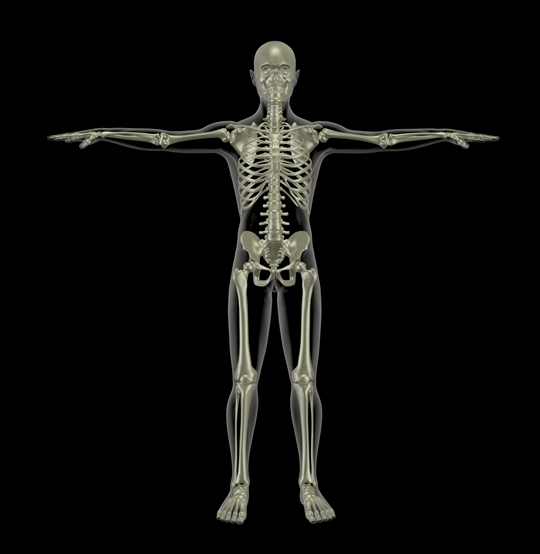

당뇨병은 발가락의 괴사부터 머릿속의 뇌졸중, 그리고 심장부터 신장까지 온 몸 구석구석에 합병증을 일으킬 수 있어 ‘침묵의 살인자’로 불린다. 당뇨합병증은 실명 원인 1위, 교통사고를 제외한 족부절단 1위, 만성신부전 1위라는 불명예를 갖고 있다.